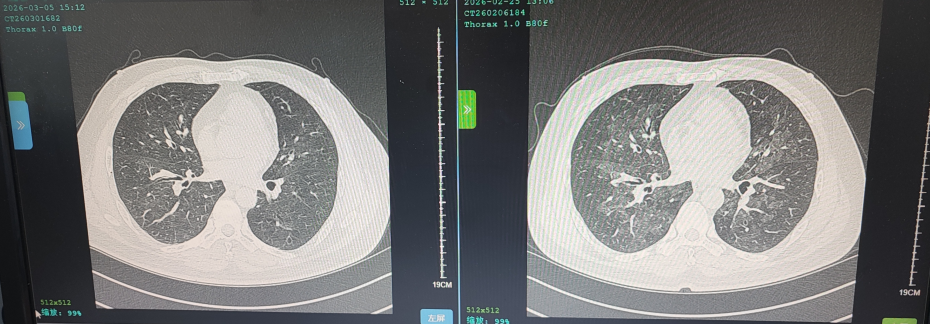

花鸟相伴本是生活雅趣,但鸟类羽毛碎屑、排泄物及粉尘中潜藏的有害物质,却可能悄然成为肺部健康的“隐形杀手”。这类疾病起病隐匿、症状不典型,极易被误诊或漏诊,严重时甚至可迅速进展为重症肺炎、呼吸衰竭,危及生命。近日,葫芦岛市第二人民医院呼吸与危重症医学科连续收治多例与接触鸟类密切相关的肺部疾病患者,为广大“养鸟一族”敲响警钟。 病例一:久咳不愈竟致呼吸衰竭 真凶竟是“养鸟过敏” 50岁的刘先生咳嗽、咳痰、气短两个月,严重时彻夜难眠,辗转求医无果,入院时已确诊I型呼吸衰竭。肺部影像学检查显示,双肺广泛存在磨玻璃影,局部已呈现“白肺”表现。此时,鉴别是感染性还是非感染性因素,成为诊断的关键。 ↑氧分压<60mmHg、二氧化碳氧分压正常、呼吸频率异常,呼吸衰竭 ↑相关检验项目正常,排除感染性因素 宋刚主任细致追问病史,发现其长期接触鸟类,结合支气管镜检查排除常见感染,最终明确诊断为外源性过敏性肺泡炎(过敏性肺炎),合并急性喘息性支气管炎。病因正是吸入鸟类羽毛及排泄物中的特异性蛋白过敏原,导致肺部过敏性炎症损伤。在脱离过敏原、接受经鼻高流量等规范治疗后,刘先生症状迅速缓解,顺利康复出院。 ↑左侧为治疗后肺部影像,右侧为治疗前肺部影像,肺炎明显减轻 病例二:高龄重症合并多重基础病 幕后黑手竟是鹦鹉热衣原体 86岁的杨大爷持续高热3天,体温达39℃,入院时已出现严重呼吸衰竭。更棘手的是,患者有20年再生障碍性贫血病史,白细胞、血小板极低,属典型免疫抑制,极易感染罕见病原菌。因血小板过低,行支气管镜检查出血风险极高。科室另辟蹊径,采用痰液NGS检测,精准锁定了致病元凶——鹦鹉热衣原体,这是一种经鸟类传播的非典型病原菌。 ↑鹦鹉热衣原体检测结果 ↑患者再生障碍性贫血,白细胞、血小板极低 诊断明确,治疗却面临两难:患者合并下肢静脉血栓,本应进行抗凝治疗,却因血小板严重低下受限。医疗团队综合研判、分层施策,严密监测血氧及肺栓塞风险,同步控制感染,并多次输注血小板、白蛋白及免疫球蛋白加强支持治疗。经综合救治,杨大爷病情好转,顺利出院。 ↑左侧为治疗前影像,右侧为治疗后影像,感染明显好转 病例三:体检发现肺部团块影 不是肺癌是真菌 患者养鸟多年,体检时发现右下肺团块状阴影,家属一度担心是肿瘤。但宋刚主任对比前年肺部影像,凭借丰富经验判断:恶性肿瘤在一年内长成如此大的团块相对少见,且病灶周围有典型晕征,高度怀疑是隐球菌肺炎——这是一种真菌性感染病,致病菌常寄生于鸟类粪便中。随后通过隐球菌荚膜多糖抗原检测,快速明确隐球菌肺炎诊断,规范抗真菌治疗后,病灶逐步缩小,病情控制稳定。 ↑隐球菌肺炎疗程较长,左侧为治疗后1个月的肺部影像,右侧为治疗前肺部影像,可见左侧晕征较右侧减轻 专家提醒:养鸟有风险 呼吸不适须警惕 宋刚主任表示,日常养鸟需做好防护: ☑ 注意环境卫生,保持通风干燥,控制粉尘; ☑ 定期清洁鸟笼与排泄物,清理时佩戴口罩、手套,避免直接接触; ☑ 老人、免疫低下、基础病较多者更需格外警惕。若出现长期咳嗽、气短、发热等症状,且有鸟类接触史,务必及时到专业呼吸科就诊,避免误诊漏诊。 我院呼吸与危重症医学科作为市级重点专科,致力于各类重症肺炎、呼吸衰竭、慢性气道疾病、哮喘等疾病的鉴别及规范化治疗,复杂疑难重症诊疗能力突出。同时携手中国医科大学附属第一医院,顶尖呼吸科专家每月定期来院出诊,让滨城百姓在家门口就能享受到省级优质医疗服务,为群众呼吸健康筑牢坚实屏障。 人民医院 人民名医 宋刚 主任医师 ·葫芦岛市第二人民医院呼吸与危重症医学科主任 ·辽宁省生命科学学会东北呼吸与危重症医学(PCCM)分会辽宁省基层委员会副主任委员 ·辽宁省细胞生物学学会放射粒子治疗专业委员会理事 ·辽宁省抗击新冠肺炎疫情先进个人 ·辽宁省预防医学会第一届吸烟相关疾病防治专业委员会委员 ·葫芦岛市劳动鉴定委员会专家库成员 ·葫芦岛市医学会呼吸内科学分会第三届委员会副主任委员 专业特色:擅长呼吸系统疑难及急危重患者的救治,如急慢性支气管炎、支气管哮喘、慢性阻塞性肺疾病、肺炎、肺栓塞、肺癌、间质性肺疾病、睡眠呼吸暂停综合征等,尤其擅长有创无创机械通气、支气管镜下相关检查及治疗(TBNA、气道支架置入术、球囊扩张等)、全肺灌洗术等领先技术,发表国家级期刊多篇。 出诊时间:每周二、周四全天 出诊地点:门诊二楼东侧35诊室 咨询热线:0429-8010115